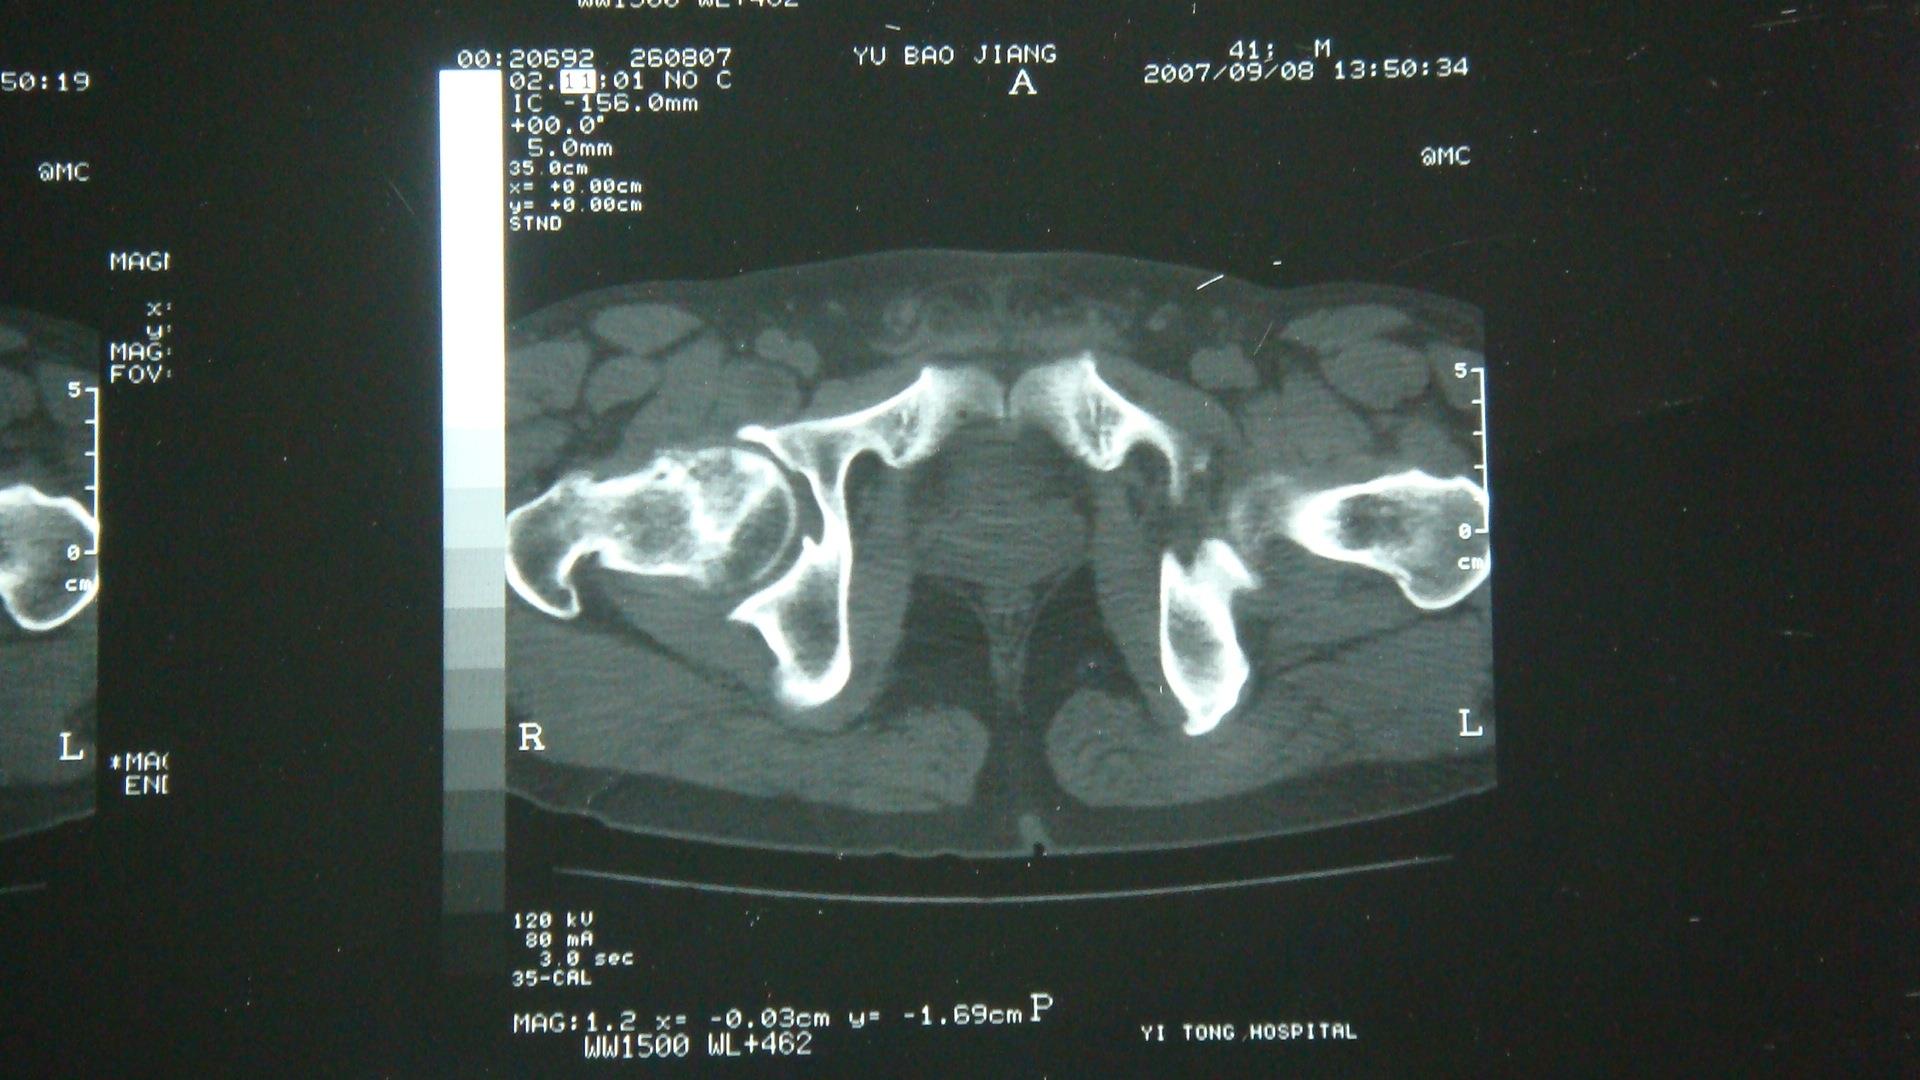

双侧股骨头X光片,CT片表现:左侧股骨头、髋关节形态正常,未见异常密度影,右侧股骨头无菌性坏死多年后,外伤(此次)见右侧股骨头变扁,密度增高,其内见多发囊变,并可见一侧股骨头下骨折线(CT明显),轻度成角,关节间隙大致正常。外伤前(2007-9-8)CT片未见明显横行骨折线。诊断:1、右股骨头无菌坏死后外伤,伴股骨头下骨折。2、左股骨头未见异常。

于某2008年8月27日外伤后CT片可见右股骨头下横行骨折线,而该患此前(2007年9月8日CT片)存在右侧股骨头无菌性坏死并有囊性变,但未见有骨折线。股骨头无菌性坏死又叫股骨头缺血性坏死或股骨头坏死。此病的发病机理为在多种原因的刺激下,股骨头的骨骺发生坏死,其内部生长的肉芽组织代替了原来的死骨,最终导致股骨头因密度变大而发生塌陷。因为骨质的变化,病变部位在轻微外力作用下即可发生骨折改变。因此,综合分析,如其在此期间(2007年9月8日至2008年8月27日)未受过其他外力,则考虑其右侧股骨头下骨折系此次外伤诱发所致。根据相关的鉴定原则,本案例适用间接因果关系类:是指外界各种致伤因素作用于人体患病组织、器官,在正常情况下不至于引起组织、器官解剖学结构连续性、完整性破坏及功能障碍,而在有器质性病变的基础上,使业已存在的器质性病变显示、加重。本案即是在患者原有股骨头坏死的疾病基础上,由外力诱发而形成骨折。

于某2007年9月8日影像学片